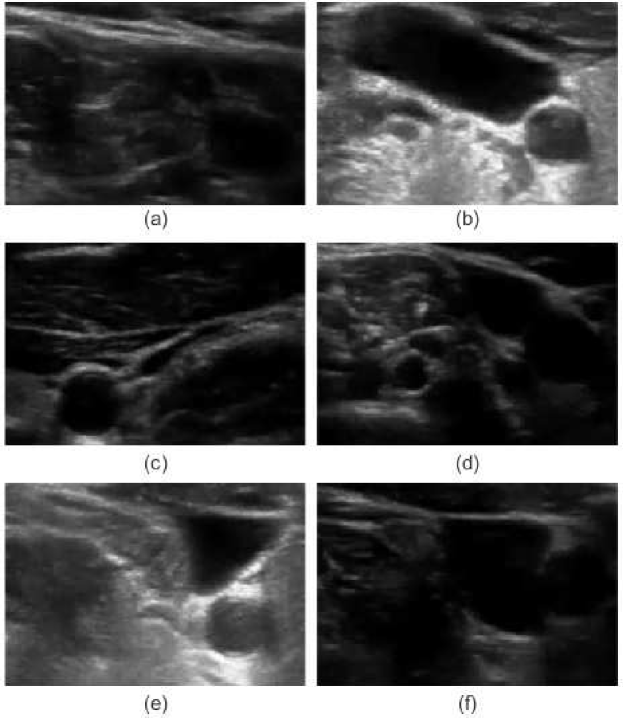

Determination of relative changes in circulating blood volume is important for a variety of acute and chronic medical conditions including hemorrhage from trauma, septic shock, dialysis and volume overload pertaining to congestive heart failure [1, 2, 3, 4, 5]. The estimation of absolute blood volume, while ideal, remains a significant challenge [6]. Recent studies suggest that non-invasive measures such as transverse ultrasound (cross-section area, CSA) of the internal jugular vein (IJV) can be used to detect and monitor relative changes in blood volume [7, 8]. As shown in Fig 1, the CSA of the IJV is dynamic with spatial and temporal variations that can correlate with relative changes in volume status. Short-term variability reflects a variety of factors including blood volume, proximity to the carotid artery, cardiac contractility, respiratory effort and local anatomy. Changes in parameters over the long-term can reflect relative changes in blood volume. Demonstration of short- and long-term CSA variability of a healthy patient sitting at different angles of inclination to simulate relative changes in circulating blood volume is shown in Fig. 2. Accurate segmentation and tracking of the rapidly changing IJV is fundamental to the use of ultrasound to estimate relative changes in blood volume.

In the case of broken edges, active contours fail to resolve the contours of intersecting objects resulting in leakage. An active shape model (ASM) using a statistical shape model can be used to address the above mentioned problem [33, 34]. Unfortunately, as per Fig. 1, the IJV assumes many different shapes and therefore, ASM is not applicable for the IJV segmentation. Other common approaches, such as Kalman filers, have been proposed for real-time vessel tracking in ultrasound imagery; however, similar to ASM, they require the geometry of the vessel [35].